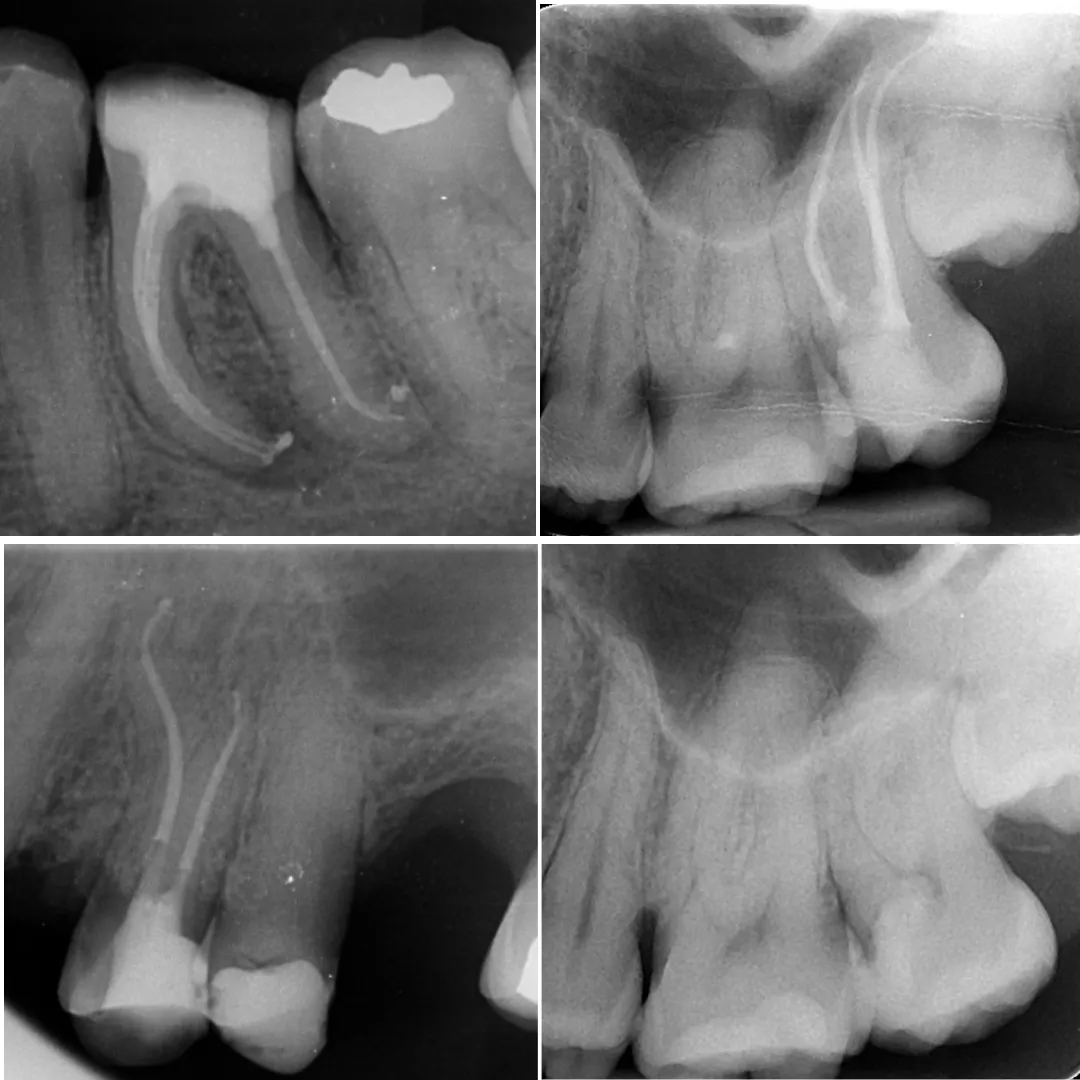

• Management of curved canals, calcified canals, and difficult access cases.

• Re-treatment cases of non-healing or failed root canals.

• Managing perforations, ledges, or instrument separation.

• Managing post space failures and disassembly of old crowns/cores.

• Advanced use of CBCT and magnification (microscope) for navigation.